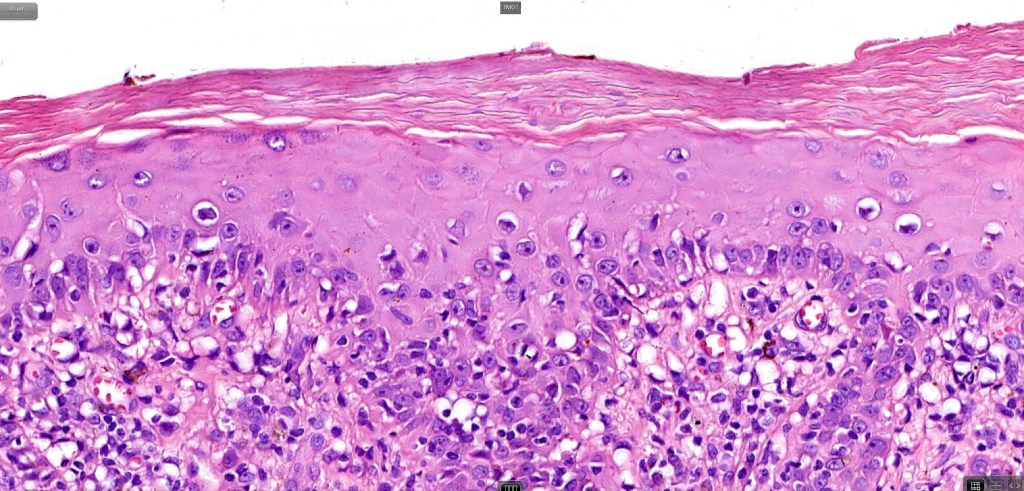

•Hyperkeratosis +/- parakeratosis

•Wedge-shaped hypergranulosis

•Generally irregular (sometimes saw-tooth) acanthosis but may show broad acanthosis

•Interface change

•Conspicuous cytoid bodies

•Pigment incontinence

•Band-like or perivascular infiltrate of lymphocytes, histiocytes with occasional eosinophils & plasma cells